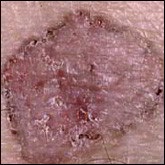

Carcinomes épidermoïdes.

Ils se situent souvent au niveau des régions exposées au soleil (tête et cou, décolleté, haut du corps, avant- bras, mains et ongles), mais peuvent toucher d’autres zones comme la bouche ou les organes génitaux. Sur la peau exposée au soleil, ils débutent souvent comme une croûte blanche (kératose actinique ou kératose solaire) qui s’épaissit progressivement et s’ulcère pour former une plaie irrégulière à bordure surélevée.